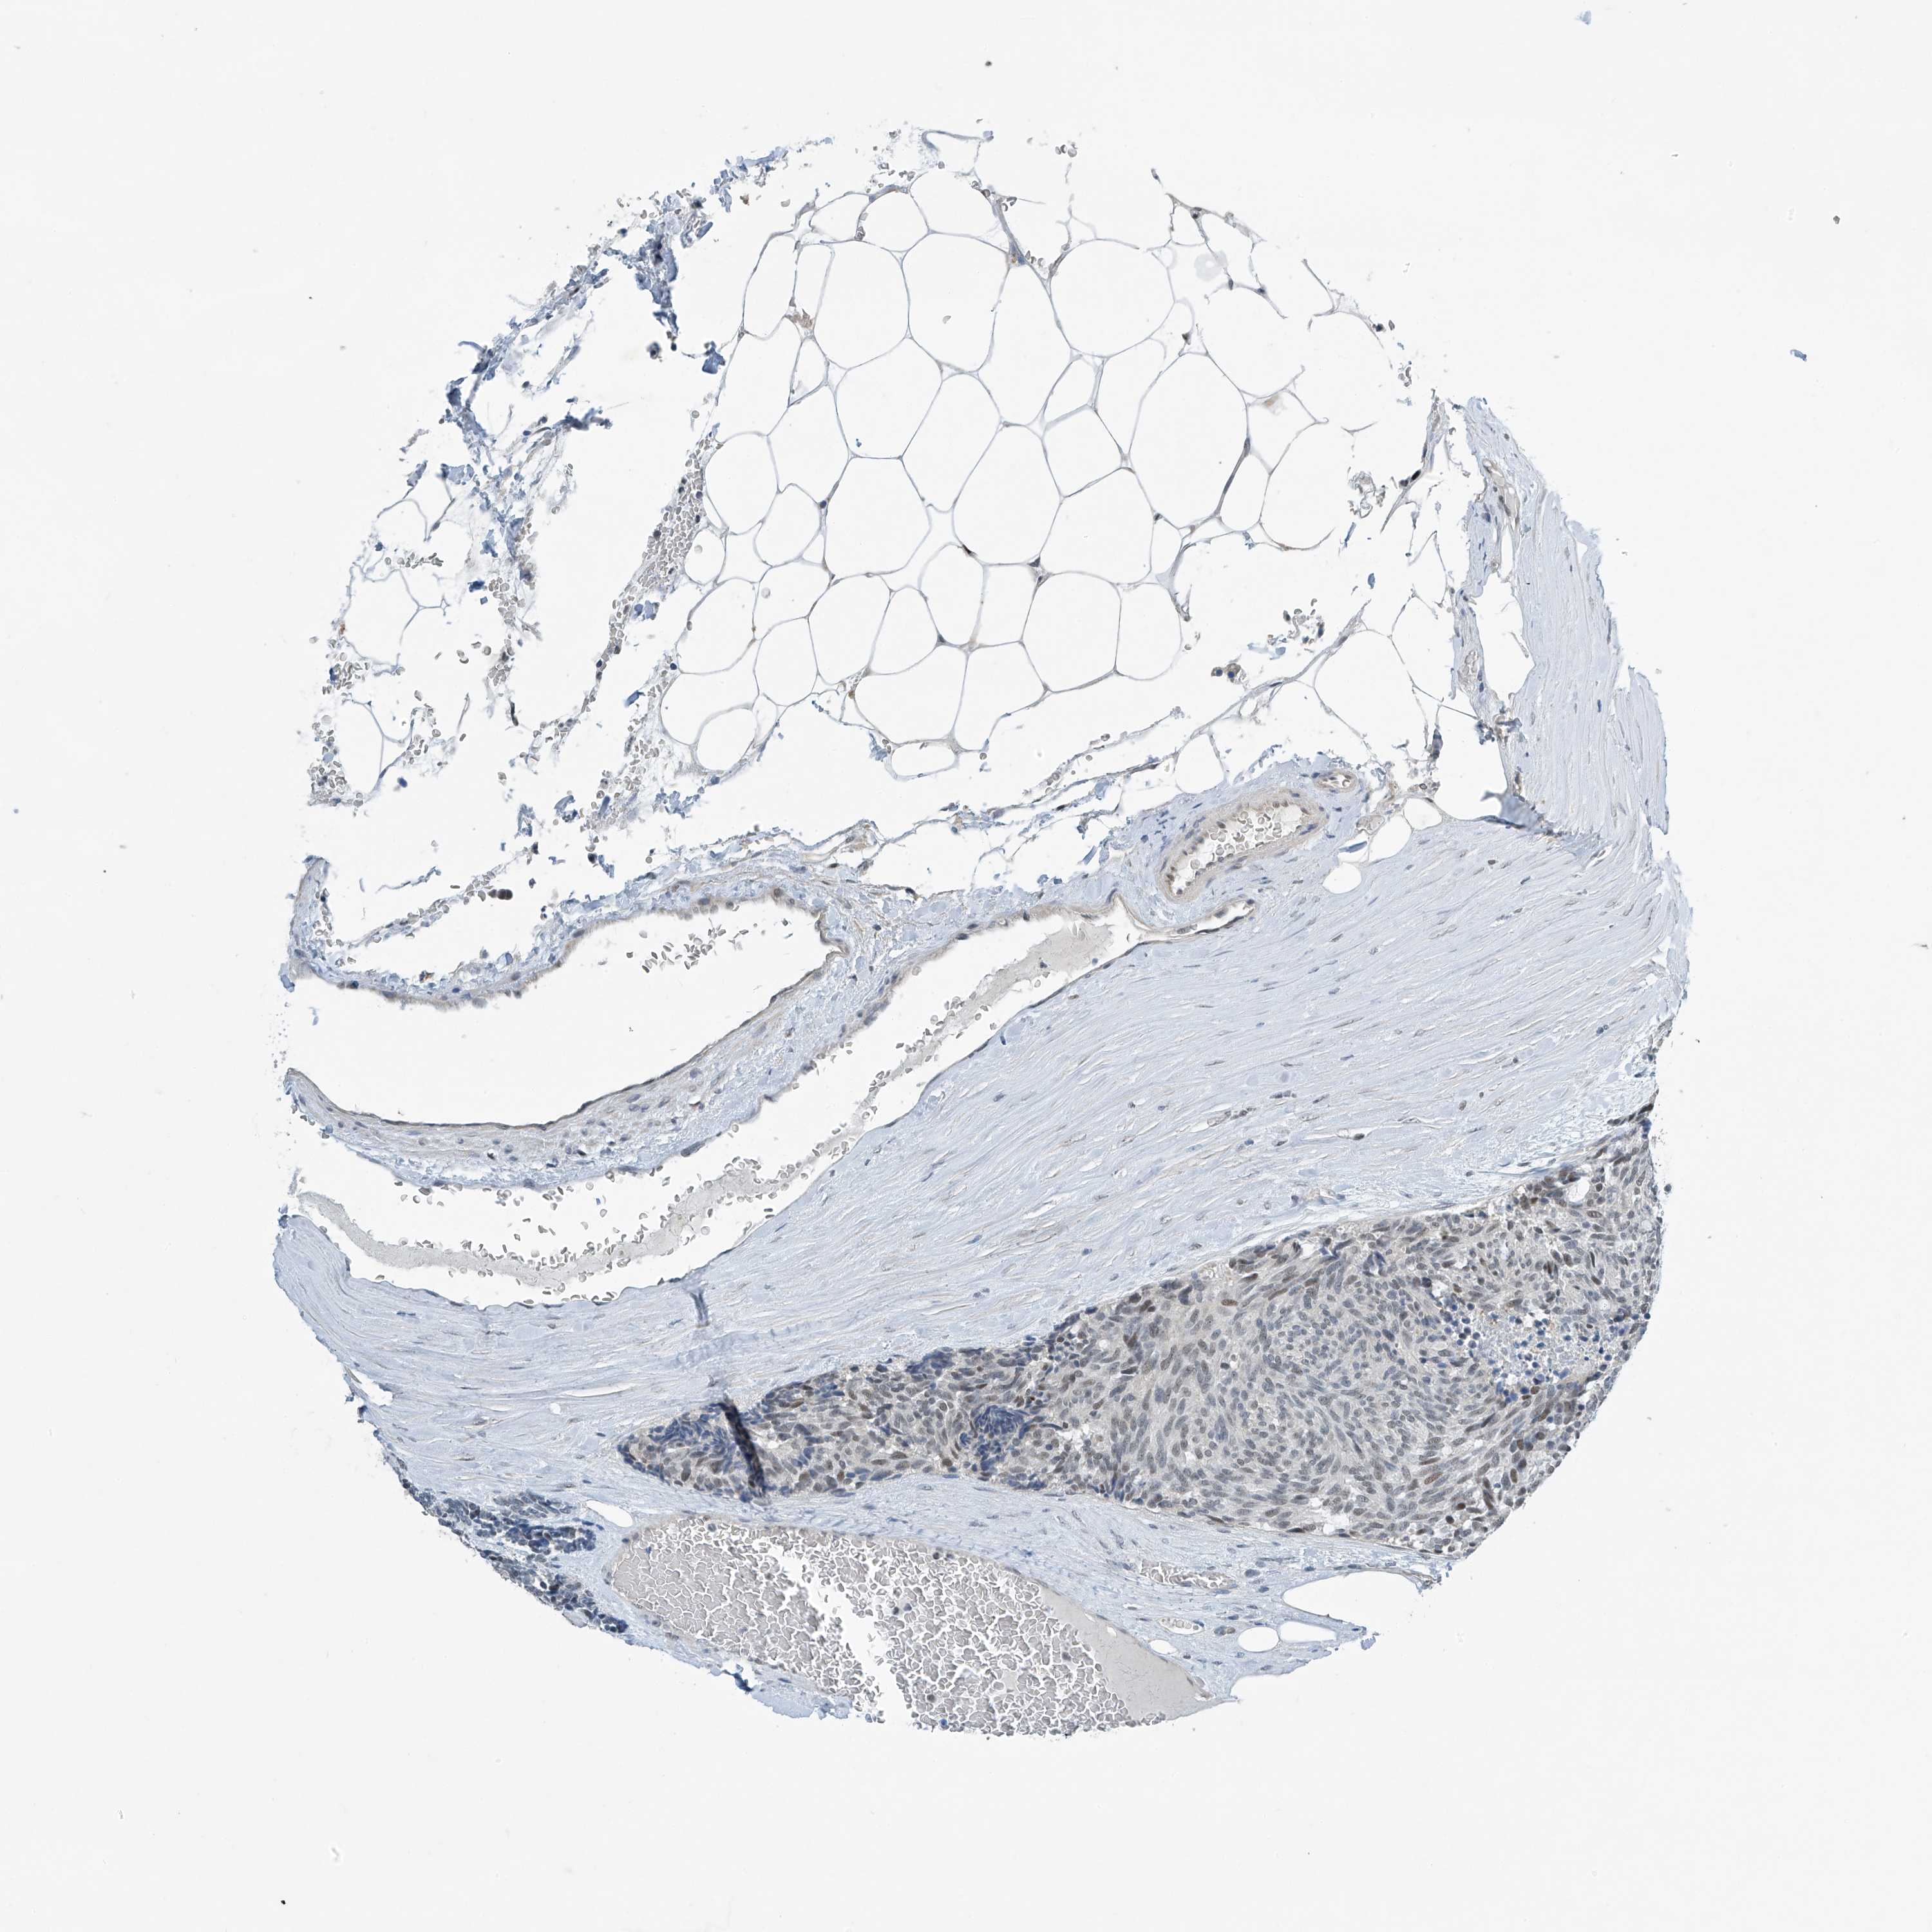

CARCINOID - Protein expressioni

A mouse-over function shows sample information and annotation data. Click on an image to view it in a full screen mode. Samples can be filtered based on level of antibody staining by selecting one or several of the following categories: high, medium, low and not detected. The assay and annotation is described here.

Each image is clickable and will lead to virtual microscopy that enables deeper exploration of all samples and also displays staining intensity scores, fraction scores and subcellular localization as well as patient and tissue information for each sample.

Antibody HPA031734

Staining

High

Medium

Low

Not detected

Intensity

Strong

Moderate

Weak

Negative

Quantity

>75%

75%-25%

<25%

None

Location

Nuclear

Cytoplasmic/membranous

Cytoplasmic/membranous,nuclear

Carcinoid, malignant, NOS